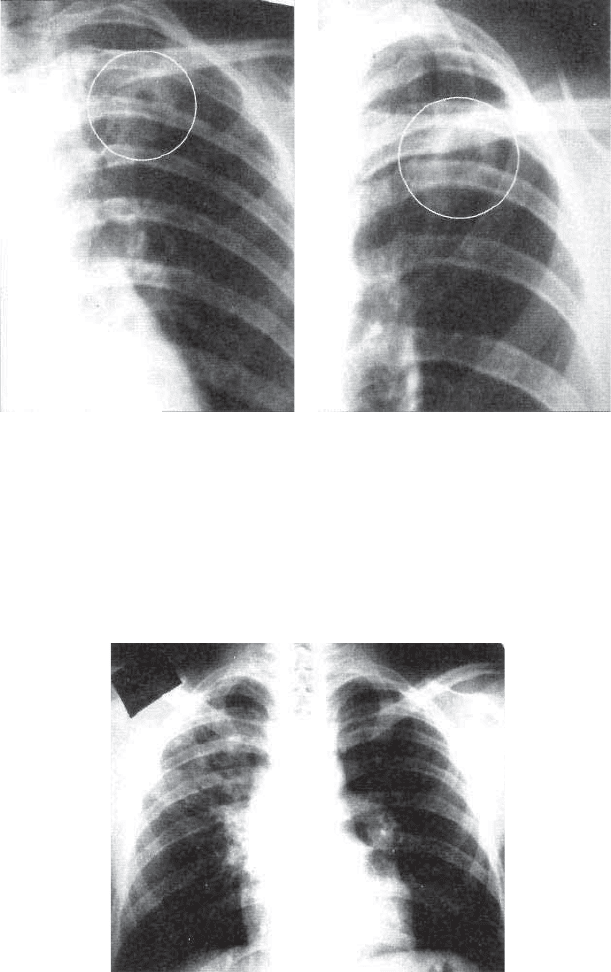

фиброзных изменений. Тень туберкулезного инфильтрата в рент-

генологическом изображении неоднородная, в окружающей

легочной ткани имеются очаги лимфогенного и бронхогенно*

го обсеменения, нередко определяется «дорожка» к корню

легкого из*за периваскулярных и перибронхиальных воспали-

бактериальная микрофлора. При рентгенологическом иссле-

довании, чаще в нижних долях легких, определяются участки

более однородной, чем при туберкулезе, инфильтрации с не-

четкими контурами. Легочный рисунок усилен и деформи-

рован.